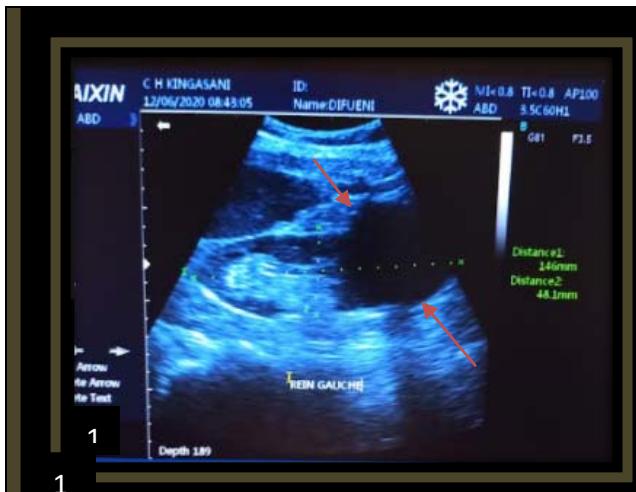

Iconography C: lower left renal polar cystic lesion, alcoholic. Image 1. showing an echo-empty (cystic) left lower renal polar mass,2. CT image showing a left lower polar hypodense mass 3. Ultra sonographic image in B mode showing subcutaneous anesthetic infiltration,4. Image of the left kidney in mode 12 months after sclerotherapy, 5. Image of a clear liquid that had been removed during sclerotherapy.